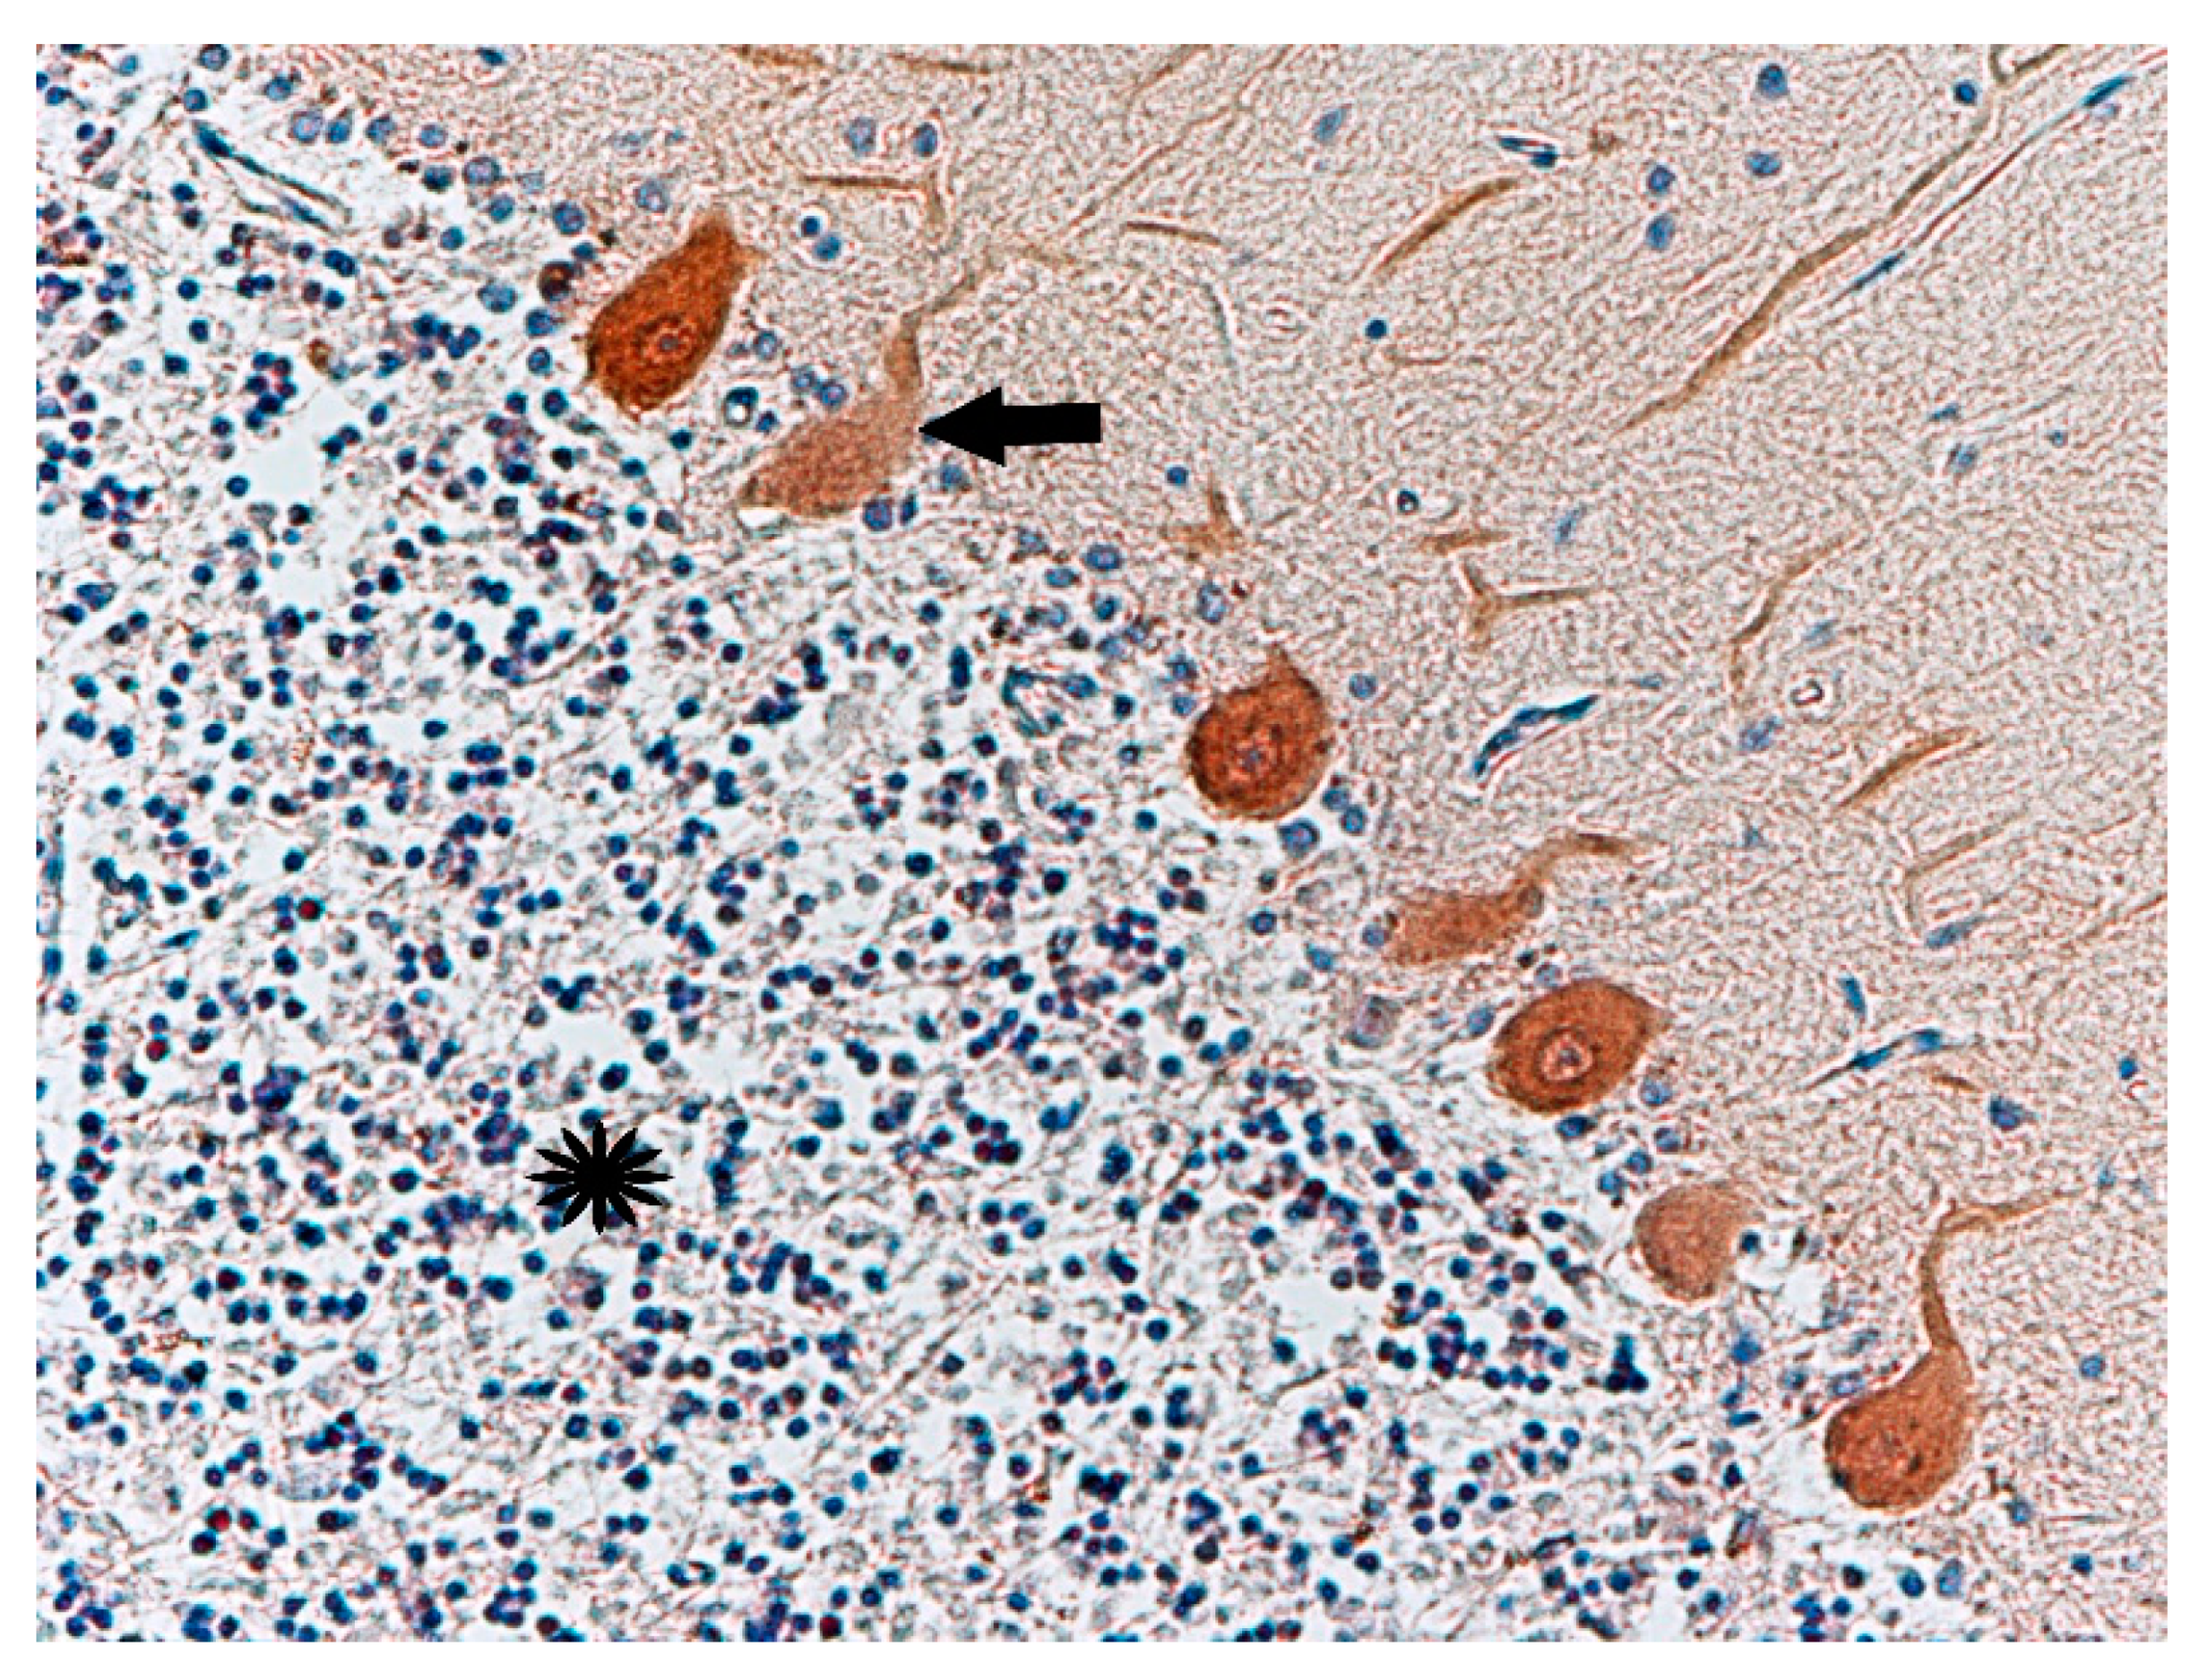

Histochemical Methods